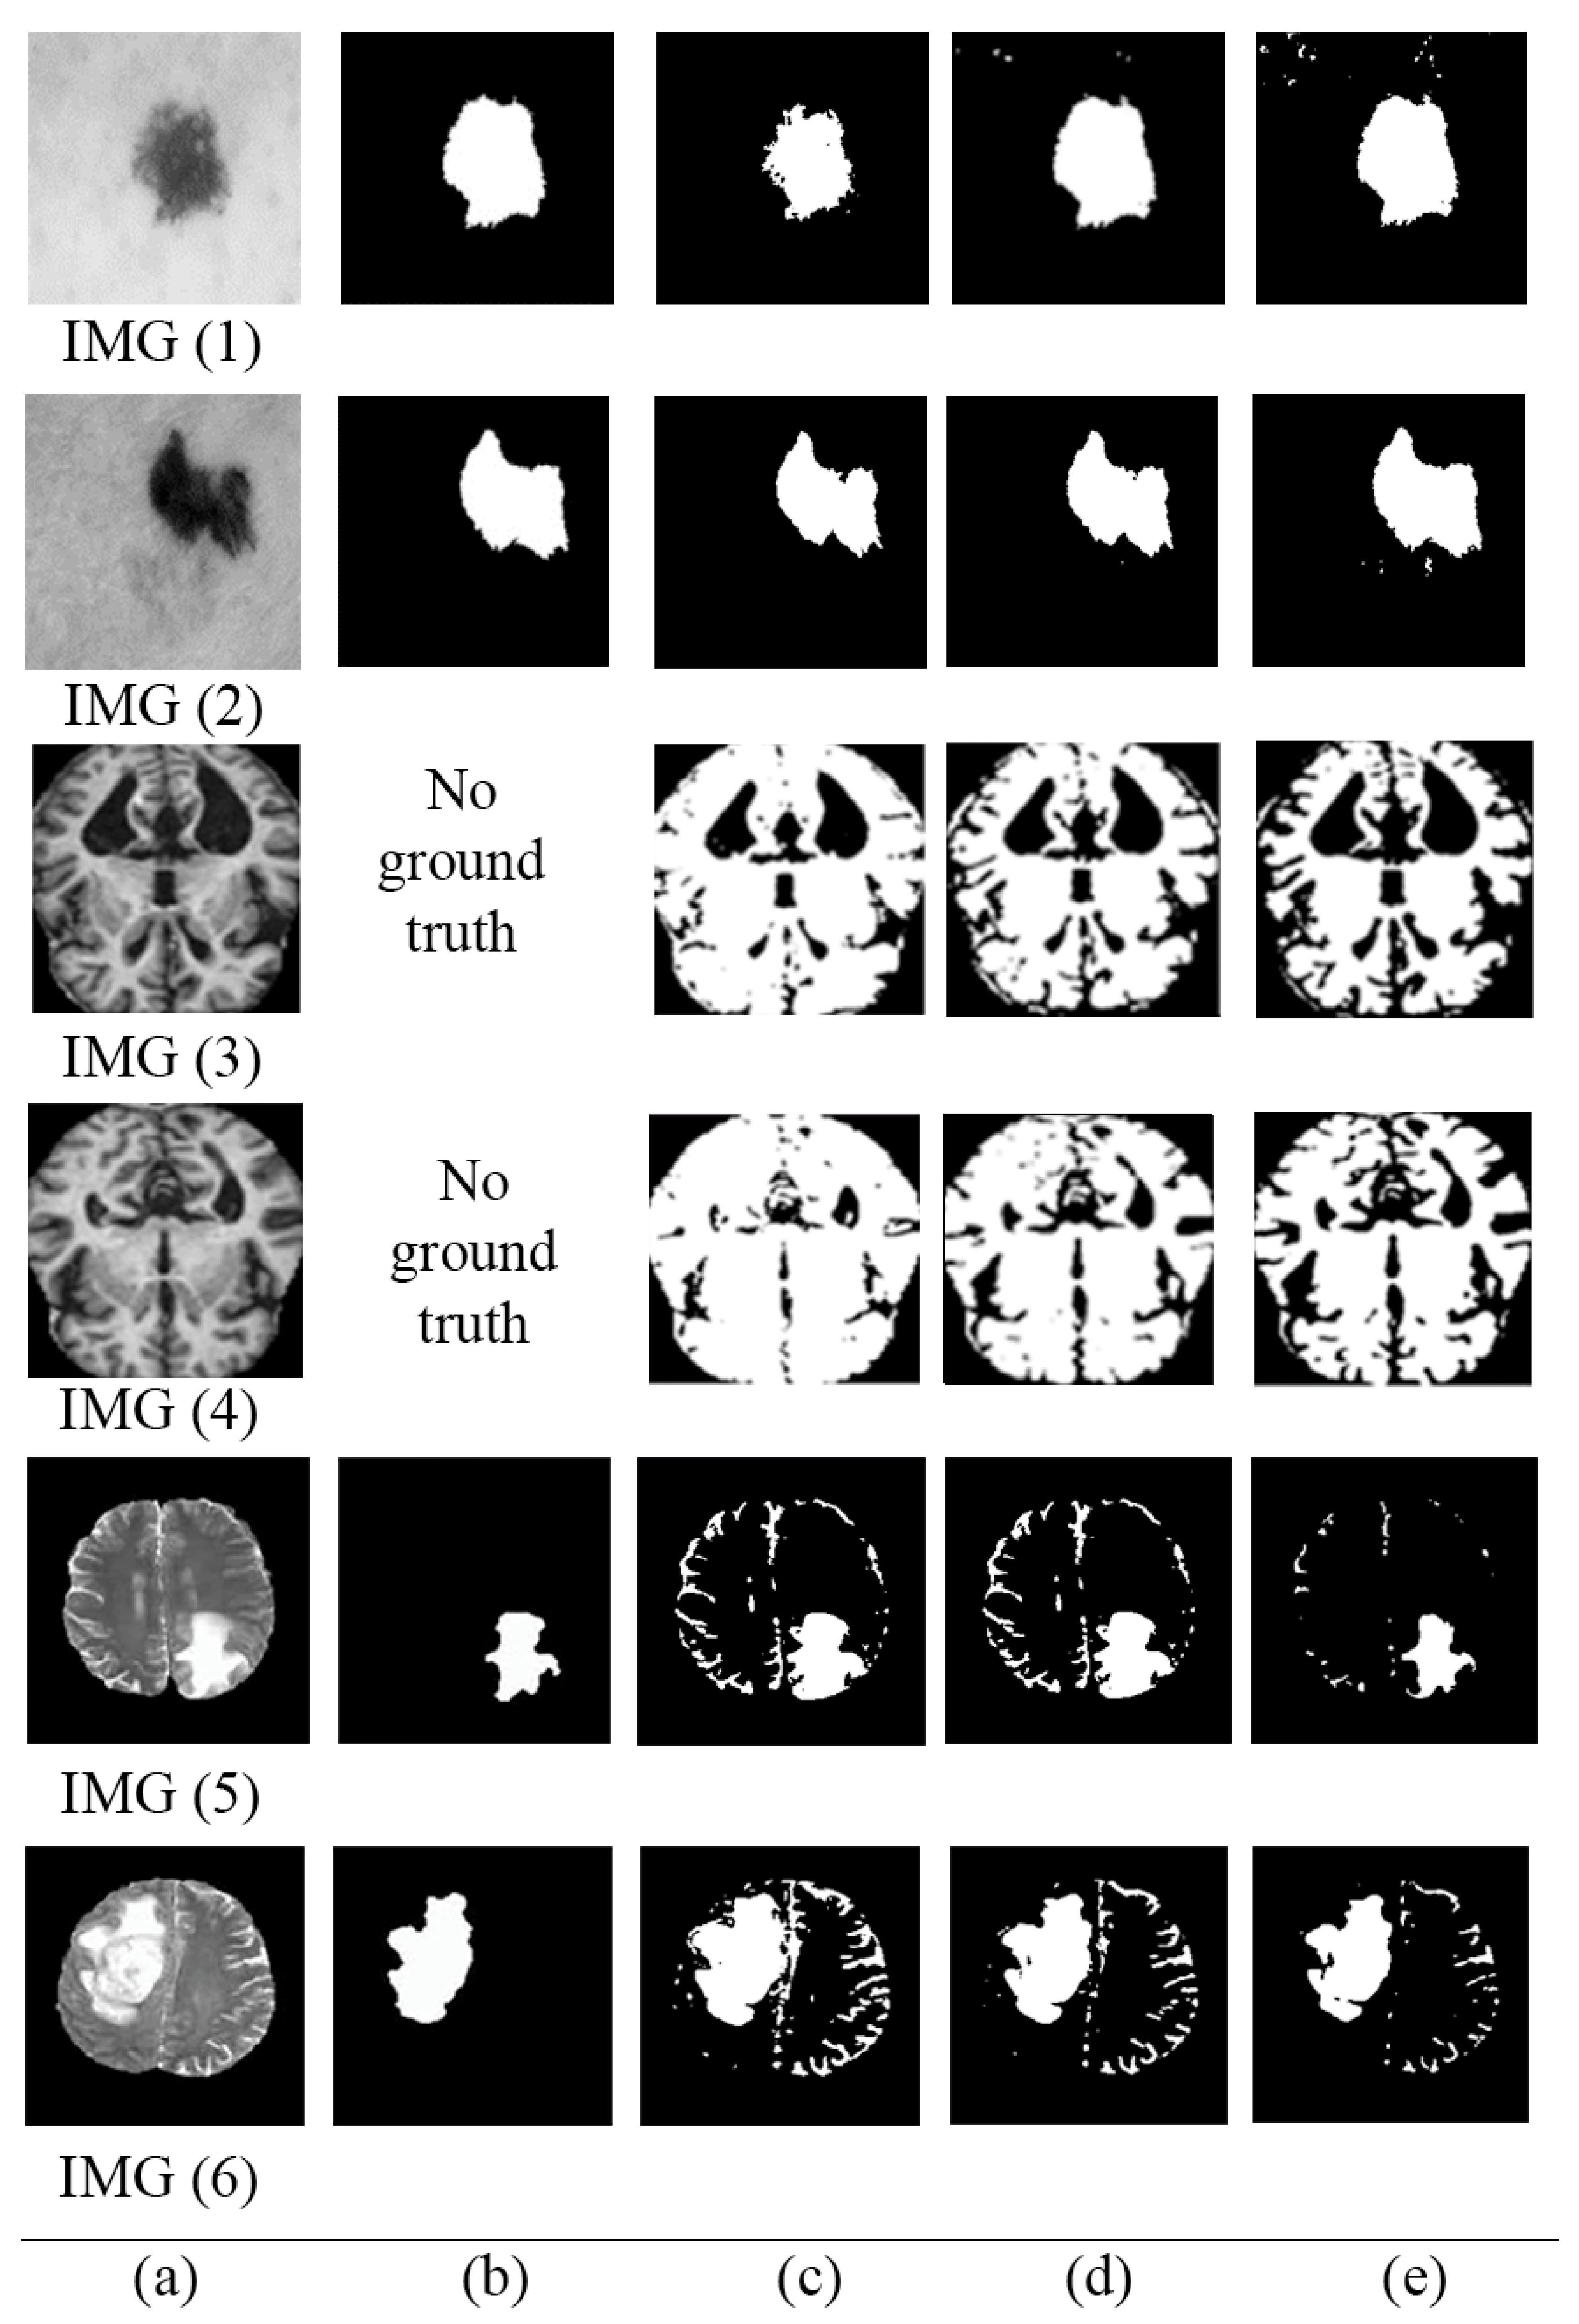

Figure 6 shows randomly selected images and their corresponding segmentation results. Figure 6a–e shows original images, ground truths, and segmented images using the original MECT, segmented images using MCET based on homogeneous mean filters approaches, and segmented images using the proposed MCET based on heterogeneous mean filter approaches, respectively. Table 5 shows the performance measured using supervised and unsupervised evaluation for segmented images in Figure 6.

Figure 6. Samples of segmented images (a) original images, (b) ground truths, (c) segmented images using the original MECT, (d) segmented images using MCET based on homogeneous mean filter approaches, (e) segmented images using the proposed MCET based on heterogeneous mean filter approaches.

Table 5. Average performance measures for the selected images in Figure 6, columns (A) refer to supervised evaluation; columns (B) refer to unsupervised evaluation.

ClassicalHomogeneousHeterogeneous

ABABAB

IMG (1)0.887240.845330.916130.882760.918240.88525

IMG (2)0.890530.851860.911050.879870.921500.89816

IMG (3)-0.80779-0.89926-0.91977

IMG(4)-0.82581-0.90140-0.90996

IMG (5)0.814480.807790.918000.899260.938950.91977

IMG(6)0.840330.825810.917720.901400.924070.90996